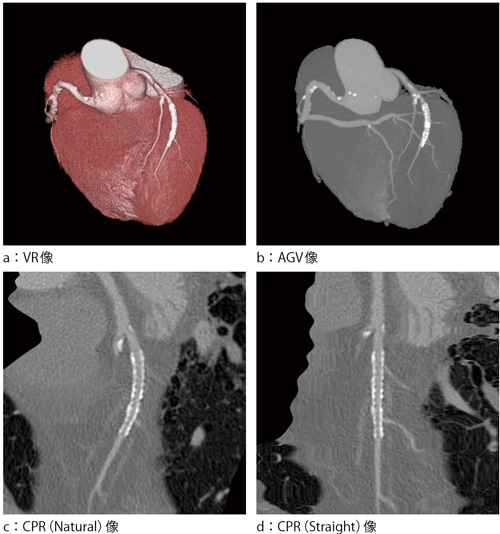

Retrospective ECGモードは,心臓の動きに対して,時間分解能を向上させるためにセグメント再構成が可能なピッチのボリュームスキャン(らせんスキャン)を行う心電同期撮影である。図4に臨床例を示す。被検者の心拍数から,最適なセグメント数やスキャン時間,テーブルピッチを自動設定する機能がある。不整脈や心拍変動が大きい場合には,ECG Editor(心電図編集機能)を用いて,心電波形や再構成位相などの編集が可能である。多少の心拍変動にも対応できる反面,被ばくが大きくなる傾向にあるので,IntelliCenterが有効である。

図4 臨床例(ステントと石灰化)